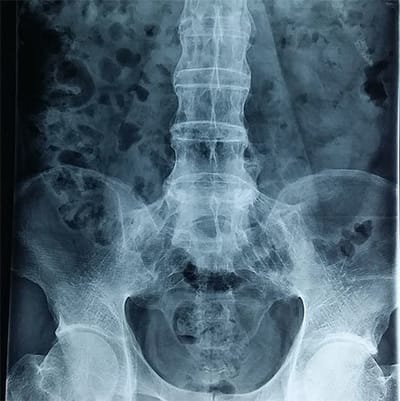

Nguyen nhan gay thoai hoa khop

Sự hư hỏng vùng đệm giữa các khớp xương ảnh hưởng nhiều đến vận động, gây đau nhức được giới chuyên môn gọi là thoái hóa khớp

Jex - Benh thoai hoa khop la gi

Viêm xương khớp là dạng viêm khớp phổ biến nhất và là một bệnh thoái hóa khớp. Bệnh này có nhiều khả năng ảnh hưởng đến mọi người khi họ già đi và là nguyên nhân phổ biến nhất

Hieu ve benh xuong khop - jex.com.vn

Thoái hóa khớp là căn bệnh khiến các khớp bị đau nhức và cứng khớp. Tình trạng này, viết tắt là OA, là một dạng viêm khớp phổ biến